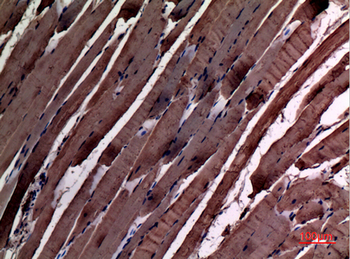

α-SMA Polyclonal Antibody

Catalog Number: orb1411650

| Catalog Number | orb1411650 |

|---|---|

| Category | Antibodies |

| Description | Rabbit polyclonal antibody to α-SMA. |

| Clonality | Polyclonal |

| Species/Host | Rabbit |

| Conjugation | Unconjugated |

| Reactivity | Human, Mouse, Rat |

| UniProt ID | P68133 |

| Tested applications | IHC-P, WB |

| Dilution range | WB: Western Blot: 1/500 - 1/2000. IHC-p: 1:100-300 ELISA: 1/20000. Not yet tested in other applications. |

| Storage | Maintain refrigerated at 2-8°C for up to 2 weeks. For long term storage store at -20°C in small aliquots to prevent freeze-thaw cycles |

| Alternative names | ACTA1; ACTA; Actin, alpha skeletal muscle; Alpha-a Read more... |

| Note | For research use only |